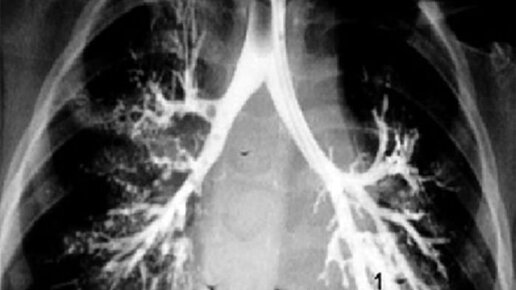

Бронхоскопия представляет собой исследование бронхов с использованием прямых или гибких бронхоскопов. Оно проводится для изучения состояния слизистой оболочки и последующего выявления признаков воспаления. Процесс бронхоскопии проходит с использованием гибкого стержня, изогнутого на конце, который называется бронхофиброскопом. Управляется он при помощи рукоятки. Показания к назначению Назначается бронхоскопия легких для того, чтобы провести диагностику и лечение патологий трахеобронхиального дерева...

КТ виртуальная бронхоскопия (или мультиспиральная компьютерная томография бронхов и легких, КТ бронхография легких) является современным способом диагностики, который предполагает применение рентгеновских лучей для сканирования бронхов и легких...

Бронхоскопия — это медицинская процедура, в ходе которой в легкие и дыхательные пути вводится небольшая камера для их осмотра. Она используется для диагностики и лечения различных заболеваний, таких как рак легких, пневмония, бронхит, астма и другие заболевания легких. В этой статье мы обсудим, что вы должны знать перед проведением бронхоскопии. Подготовка: перед проведением бронхоскопии врач подробно обсудит с вами процедуру, чтобы вы понимали, чего ожидать. Он также рассмотрит все имеющиеся у вас медицинские заболевания, которые могут повлиять на вашу реакцию на процедуру или ее результаты...